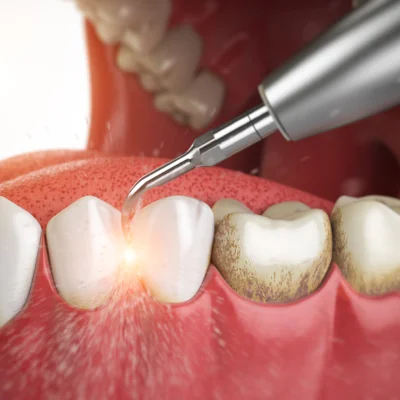

- การขูดหินปูน